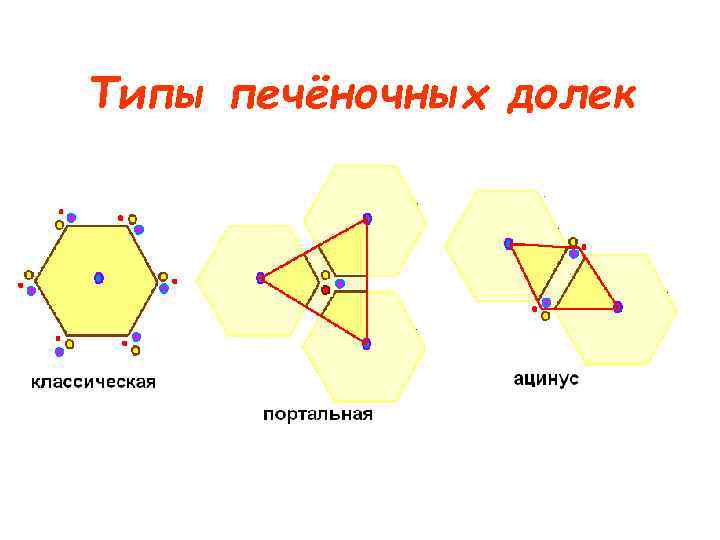

Типы печёночных долек

Типы печёночных долек